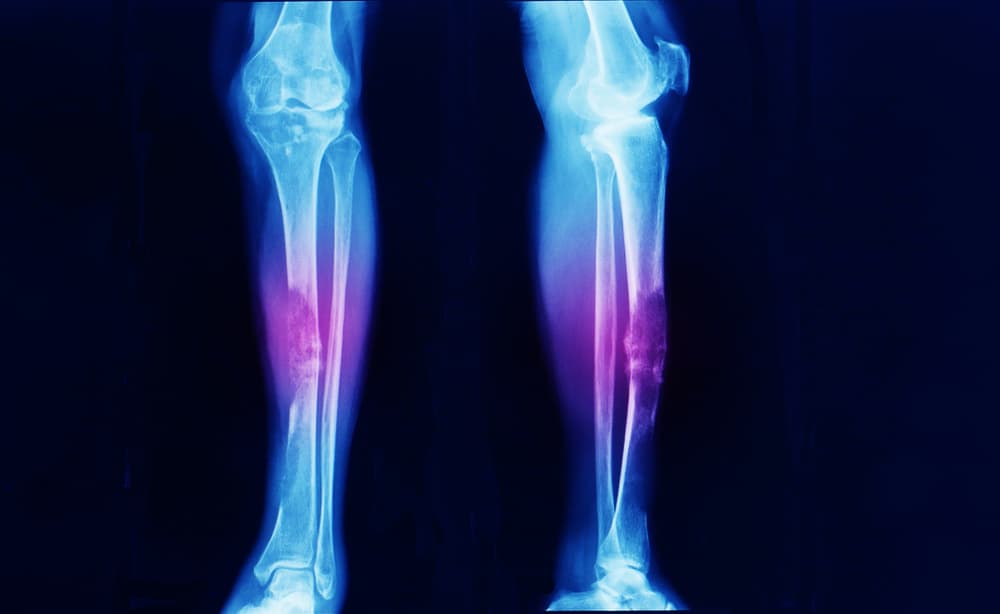

Bago gamutin ang cancer sa buto, susubukan ng mga doktor na malaman ang lawak ng cancer. Karaniwan itong ginagawa sa pamamagitan ng x-ray, dahil nakikita dito ng mga doktor ang pinsalang ginawa ng cancer sa buto.